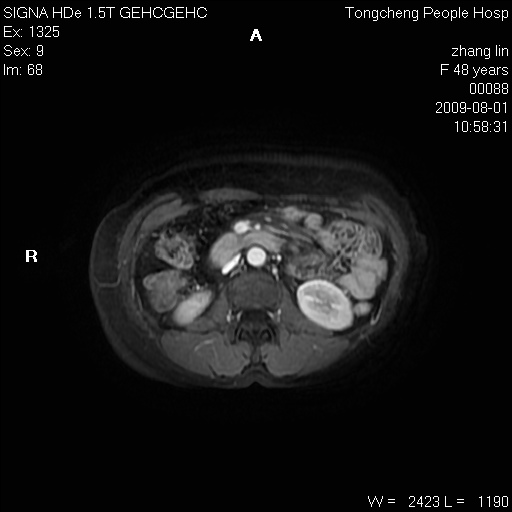

女,48岁。健康体检,彩超发现右肾占位性病变。平素健康。

临床诊断:右肾占位性病变,性质待定(囊肿?肿瘤?)。

上中腹部mr平扫+增强扫描,图像如下:

右肾上极见一类圆形病灶,t1wi呈等信号t2wi呈等高混杂信号,三期增强无强化,边界清---考虑囊肿出血。

同反相位均表现为等信号,病变无强化,考虑含蛋白的囊肿可能,弥散加权相或许有些帮助,

肝囊肿

慢性胆囊炎